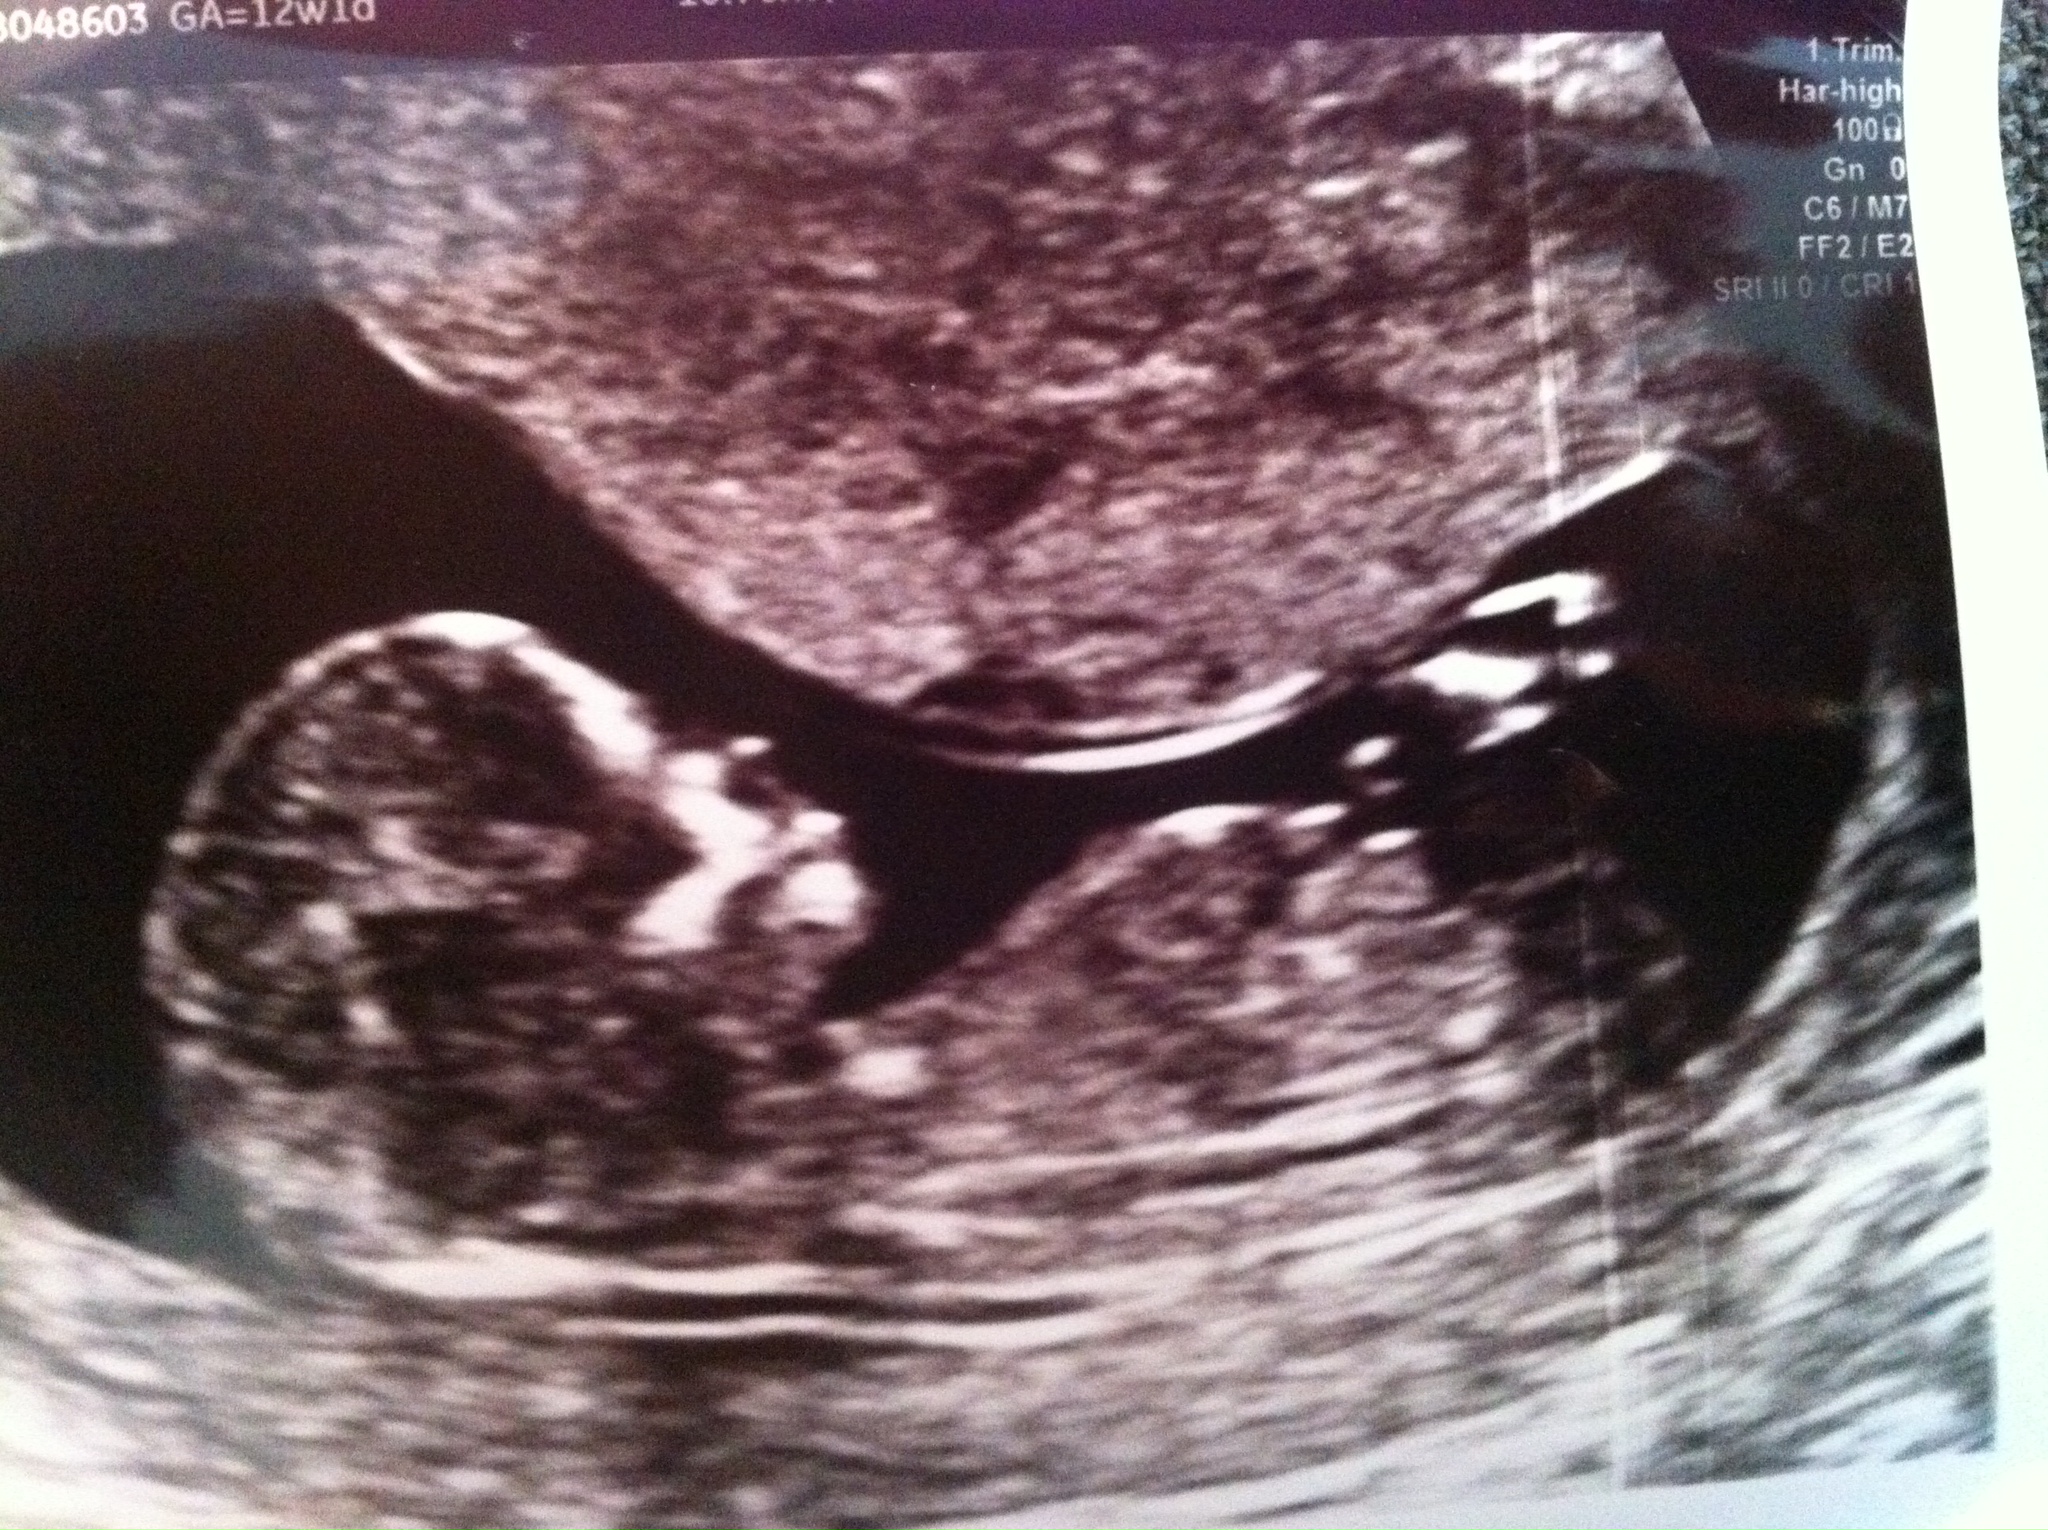

Nub at 13 weeks:

Attachment 20054